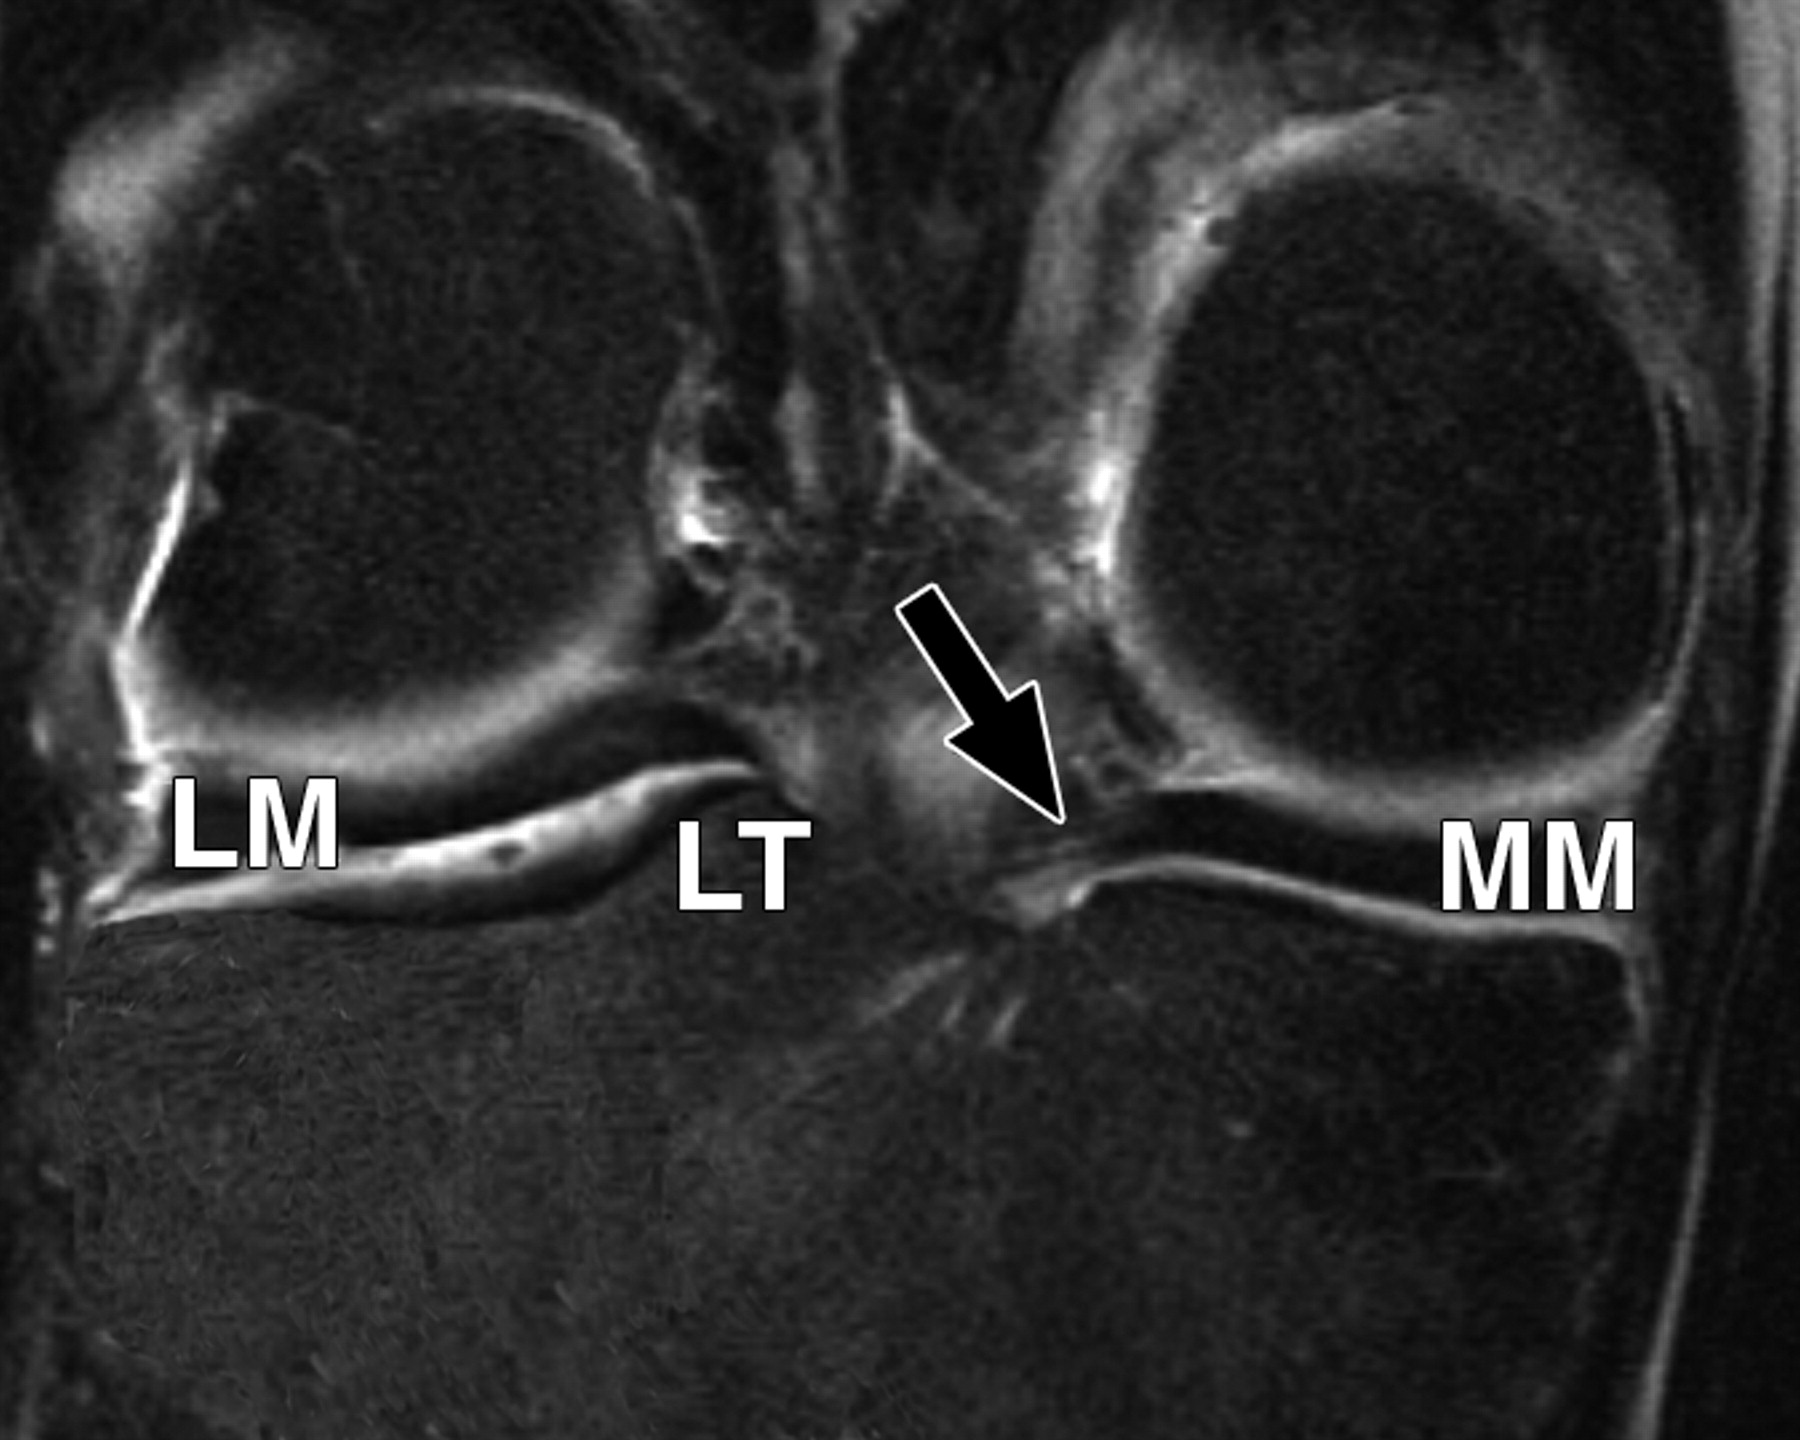

图5A-59岁男性。

中等加权、脂肪饱和、快速自旋回波(TR/TE有效值,3,700/29)3-T MR图像显示半月板后根和交叉韧带的解剖关系。

冠状面MR图像显示内侧半月板(MM)后根(箭头)覆盖后髁间区域的一个以上切片厚度。LM =外侧半月板。LT =胫骨外侧结节。

5520cf3c3107bcbe16a450c0ac30f232.jpeg

图5 B-59岁男性。中等加权、脂肪饱和、快速自旋回波(TR/TE有效值,3,700/29)3-T MR图像显示半月板后根和交叉韧带的解剖关系。

冠状面图像依次位于A的腹侧,显示外侧半月板后根(LM)(白色箭头)和内侧半月板后根(MM)(黑色箭头,B)的插入,覆盖后髁间区域的一个以上切片厚度。MT =胫骨内侧结节。